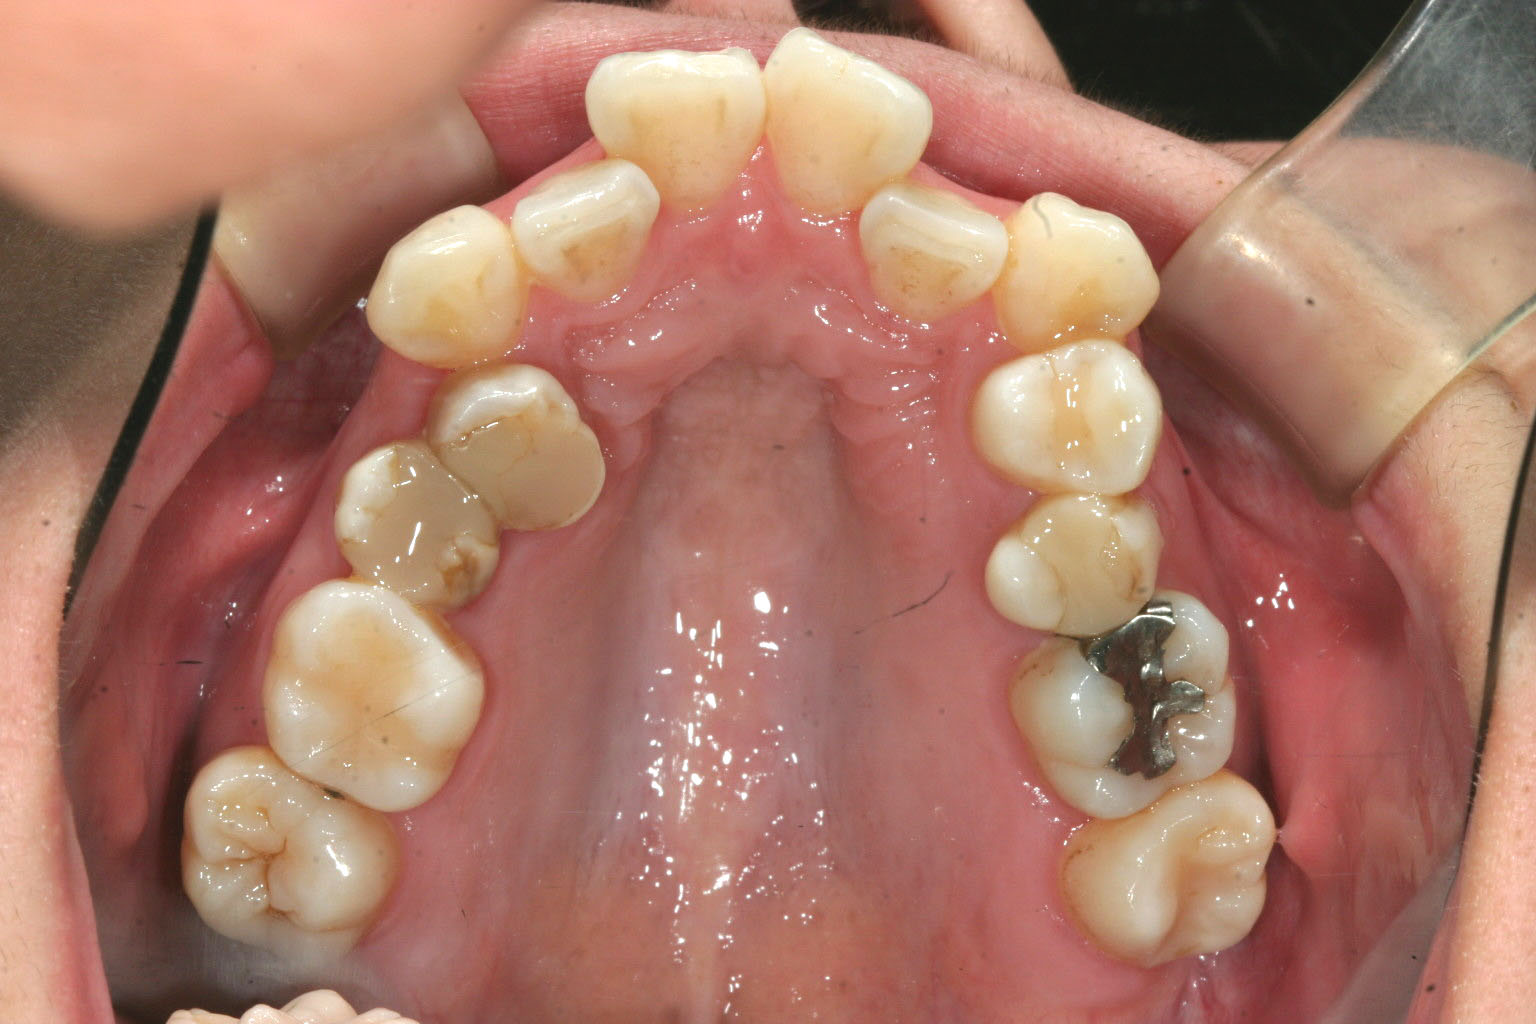

アーチが狭く犬歯が飛び出してかなりのガタガタです。

左右の小臼歯を抜歯する事で前突を改善し、又アーチを広げました。